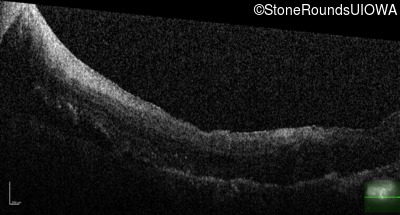

Age at visit: 43 years (Visit 2)

This 43 year old woman first experienced a slight loss of visual acuity at age 23. Fluorescein angiography at that time revealed some vascular leakage from the optic discs and peripheral retina. The maximum combined response of the ERG revealed a selective loss of the b-wave.